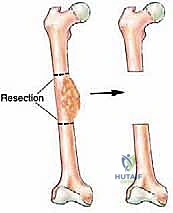

1. استئصال الأورام العظمية (Bone Tumors)

عند إصابة المريض بورم عظمي خبيث أو حميد شرس (مثل الساركوما العظمية)، يتطلب العلاج استئصال الورم مع مسافة أمان من العظم السليم لمنع انتشار السرطان. هذا يترك فجوة عظمية هائلة. استخدام الشظية الوعائية يسمح بإعادة بناء الطرف بدلاً من بتره.

المرحلة الثالثة: تحضير موقع الاستقبال (Recipient Site Preparation)

في الطرف المصاب (سواء كان الفخذ، القصبة، أو الذراع)، يتم تنظيف الفجوة العظمية بالكامل وإزالة أي أنسجة ميتة أو ندبات. ثم يتم تحديد شريان ووريد سليمين في هذه المنطقة لاستخدامهما في التوصيل.

المرحلة الخامسة: التثبيت والإغلاق (Fixation and Closure)

يتم تثبيت الشظية المزروعة بقوة مع نهايات العظم الأصلي باستخدام شرائح معدنية ومسامير أو مثبتات خارجية. يضمن هذا التثبيت الميكانيكي استقرار العظم حتى يكتمل الالتئام البيولوجي.